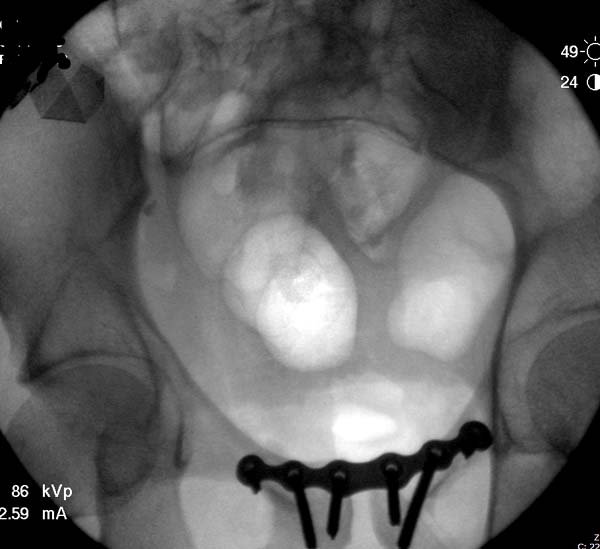

До операции желательно выставить все стандартные снимки: обзорный таза,

вход + выход. А популярный у всех 3Д используется только для общего

обзора, но не для детального изучения. Обычно КТ“для

диагностики-стандарт, а послеоперационно - дополнительный расход”. Лучше

обычные рентген-снимки, но бывают исключения, когда на снимке имеются

неясности, например, винт через сакральный форамен или через сустав!

Здесь примеры фиксации с различными вариантами.... .